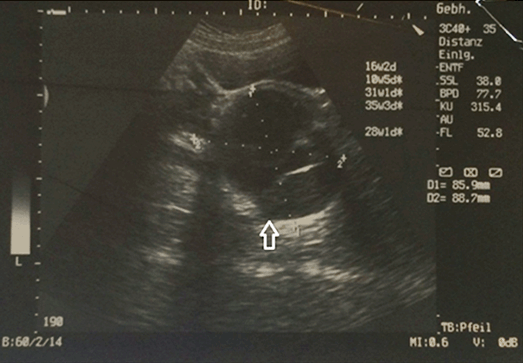

Case Series: In the first patient (aged 19 years), pelvic ultrasonographic examination showed a large (85.9×88.7 mm) multiloculated complex cyst posterior to the cervix. No evidence of recurrence was observed post-resection. The histological examination of the specimen showed mature cystic teratoma with no malignancy. The second patient (aged 16 years) was with a history of slow progressive enlargement of a non-ulcerative mass in the gluteal region. Surgery was performed. On histopathological examination, the specimen showed chronically inflamed pilonidal sinus with mature cystic teratoma. Conclusion: These two cases suggest that we should put in mind the differential diagnosis of teratoma in sacrococcygeal region masses and it can be cured with surgery if the tumor mass was completely resected with the coccygectomy. | |

Case 1 History and Examination The patient had a history of a small bulge in the perineum on the right side and a small sinus just below her coccyx during her lifetime. She had no leg pain or paresthesias, no difficulties in urination or defecation, no weight loss, and was able to walk with no difficulties. The patient had an uneventful medical and surgical history with a negative parental consanguinity and a negative family history for same. No irregularities were marked in the menstrual cycle since her menarche at 12 years. In the last two years, she had a decrease in the duration of bleeding (from seven to three days) but with a normal amount of flow. On physical examination, lower limbs revealed normal muscle tone and power, intact sensation, normal reflexes and intact sphincters and rectal mucosa, which was further confirmed by digital rectal examination. A large cystic mass was observed pushing the rectum posteriorly with the mucous membrane moving over it. Diagnostic evaluation Surgery The wound was packed with gauze flavored with iodine and left for secondary healing to take place with regular dressing till 21 days. Histopathological examination Microscopically, the sections showed mature respiratory mucosa, squamous epithelium, mucinous gland and glial elements associated with fibrofatty tissue, bundles of nerve fibers and smooth muscle. It also contained coccygeal bone. The diagnosis was mature cystic teratoma. Outcome Magnetic resonance imaging of pelvis and lumbosacral region revealed it to be free of mass with the restoration of the position of the rectum, bladder and the site of coccygectomy (Figure 4). Case 2 History and Examination The patient had a history of small sinus without discharge below the coccyx. She had no leg pain or paresthesias, no difficulties in urination or defecation, no weight loss and no walking difficulties. The patient had uneventful medical and surgical history with a negative parental consanguinity and a negative family history for same. Her menstrual cycle was regular, with no change in the amount or duration. Her menarche started at 15 years. Physical examination of lower limbs revealed normal muscle tone and power, intact sensation, normal reflexes, intact anal sphincter and normal rectal mucosa, which was further confirmed by digital rectal examination. A cystic mass was found to be pushing on the rectum posteriorly; the mucous membrane was found moving over it. Diagnostic evaluation Magnetic resonance imaging of pelvis and lumbosacral region revealed a large (17×15×10 cm) lobulated outline, hyperintense signal on T1- and T2- with a small (2×10 mm) fatty component near the coccyx, arising from the anterior of lower sacrum and extending posteriorly to the gluteal region more on the right side below the coccyx to the pelvis. It caused displacement of the rectum posterolaterally and uterus and urinary bladder anteriorly. No enhancement was seen after gadolinium contrast (Figure 5). Surgery Histopathological examination A small cyst lined by ciliated epithelial cells was found on one side and squamous epithelial cells on the other, with enteric glandular component seen in the wall of the main cyst. A piece of the bone was present. The diagnosis was chronically inflamed pilonidal sinus with mature cystic teratoma. Outcome | ||||||